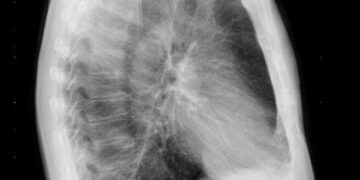

Introducción y descripción del caso

Mujer de 34 años. Es dependienta de una tienda de modas. El único antecedente clínico es artritis reumatoide desde hace 5 años, controlada con metrotrexate y sin brotes desde hace 2 años. No tiene hábitos tóxicos. Al final de una consulta rutinaria, refiere que desde hace 3 días presenta dolor abdominal bajo de tipo cólico, de intensidad leve, no relacionada con un cambio de habito intestinal, ni con trasgresión dietética, ni con alteración menstrual.

Se observa una perdida de peso leve,( 3 kg), en los últimos tres meses, aunque refiere que lleva mucho estrés en el trabajo y come mal. No presenta síndrome miccional ni fiebre ni otras sintomatologías. La exploración abdominal es anodina, se solicita hemograma y bioquímica general, test de sangre oculta en heces. Se pauta dieta y espasmolíticos, y observación domiciliaria. Al día siguiente vuelve a consultar por el dolor abdominal, aunque refiere que es más intenso, y que se va acompañado de nauseas y un vomito, y una deposición blanda con hebras de sangre. En la exploración abdominal presenta un abdomen poco depresible, dolor en fosa iliaca derecha, con Signo de blumberg positivo, por lo que se remite a Urgencias hospitalarias con diagnostico de abdomen agudo. Es valorada por el cirujano decidiéndose intervención quirúrgica, detectándose un plastron inflamatorio abscesificado a nivel de ileon distal y colon proximal, se hace resección parcial, siendo dada de alta 10 días después. Actualmente lleva 3 meses estable y sin nueva crisis.

La exploración abdominal es anodina, se solicita hemograma y bioquímica general. El test de sangre oculta en heces es negativo y en la analítica general, se percibe una discreta anemia microctica e hipocrómica. Ecografía abdominal: plastrón inflamatorio en FID que engloba apéndice y colon ascendente.